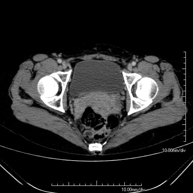

- TC Pelvis

Prueba diagnóstica que consiste en obtener imágenes bi y tridimensionales de la pelvis de alta definición anatómica (estructuras óseas, estructuras vasculares, vejiga, útero y ovarios, próstata y vesículas seminales, uréteres, etc.) mediante el empleo de un equipo de TC (Tomografía Computarizada). La mayoría de estudios requieren el empleo de contraste yodado.

- Angio-TC aorto-ilíaco

Prueba diagnóstica no invasiva que consiste en el estudio de las arterias ilíacas y la aorta abdominal obteniendo imágenes de alta definición anatómica mediante el empleo de un equipo de TC (Tomografía Computarizada) y de contraste yodado. La calidad de las imágenes permite realizar reconstrucciones en 2D y 3D gracias a estaciones de trabajo especializadas en el estudio arterial. Esta prueba está especialmente indicada como estudio pre-quirúrgico (mapa vascular) antes de intervenciones percutáneas o quirúrgicas de aorta abdominal, como el estudio complementario en pacientes con isquemia de miembros inferiores, etc.